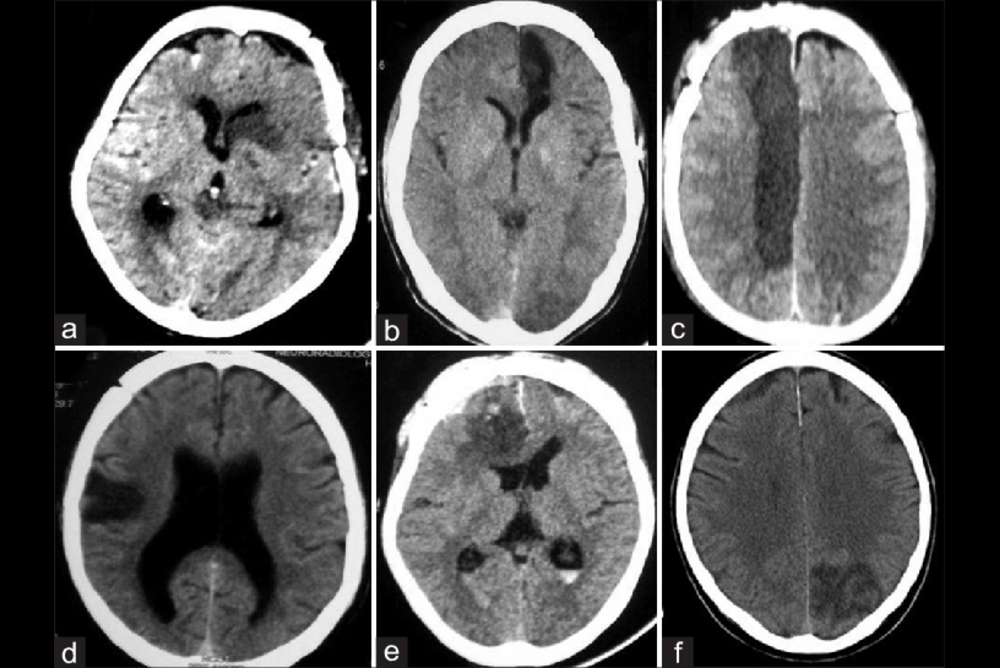

- Amount of blood: A larger amount of blood seen on the CT scan (often classified with Fisher scales or Modified Fisher scales) is strongly linked to the risk of having severe vasospasm.

- CT Angiography (CTA): Provides high-quality images of blood vessels in order to identify the areas of constriction.

- Digital Subtraction Angiography (DSA): The gold standard test that provides the most accurate picture of blood vessels in the brain. It is also utilized to aid later treatment.

- Perfusion CT/MRI: The latest imaging methods allow for the measurement of the flow of blood in various brain regions, and allow for the early detection of a decrease in perfusion caused by vasospasm.